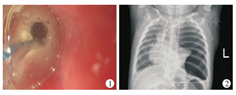

4例患儿均为男性,食管狭窄的病因分别为2例食管闭锁术后吻合口狭窄,2例食管烧伤。术中均采用导丝导引的三级球囊进行食管狭窄段的扩张操作(在胃镜直视下将球囊通过活检通道放置于食管狭窄处,往球囊内注水并维持不同的压力即可产生不同的直径)(图1);行胃镜下食管球囊扩张术的次数范围为1~12次,平均次数为5次;食管穿孔发生的年龄为8个月至2岁11个月。

4例患儿中,2例(患儿1、3)在食管扩张术中发现右侧大量气胸,1例(患儿4)在术中可见胃镜进入胸腔,1例(患儿2)于术后第二天出现呼吸困难、发热及左侧气胸(图2),均初步诊断为食管穿孔;3例在24 h内诊断,1例在48 h内获得诊断。该4例患儿的具体资料见表1。